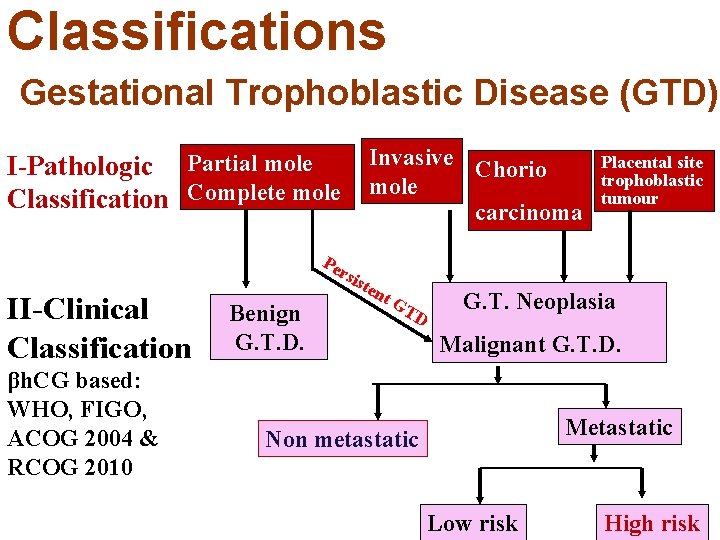

Definitions Gestational Trophoblastic Disease (GTD) It is a spectrum of trophoblastic diseases that includes: Complete molar pregnancy Partial molar pregnancies Invasive mole Choriocarcinoma Placental site trophoblastic tumour The last 2 may follow abortion, ectopic or normal pregnancy. RCOG Guideline No. 38. 2010

Definitions Gestational Trophoblastic Neoplasia (GTN) =Malignant Gestational Trophoblastic Disease It is a spectrum of trophoblastic diseases that develops malignant sequelae. GTN includes: Persistent post molar GTD Invasive mole Choriocarcinoma Placental site trophoblastic tumour The last 2 may follow abortion, ectopic or normal pregnancy. Disaia &Creasman Clinical Gynecological Oncology 2007 Cunningham et al Williams Obsterics 23 rd , 2010

Classifications Gestational Trophoblastic Disease (GTD) Invasive Chorio I-Pathologic Partial mole Complete mole Classification carcinoma Placental site trophoblastic tumour Pe II-Clinical Classification βh. CG based: WHO, FIGO, ACOG 2004 & RCOG 2010 rsi ste Benign G. T. D. nt GT D G. T. Neoplasia Malignant G. T. D. Metastatic Non metastatic Low risk High risk